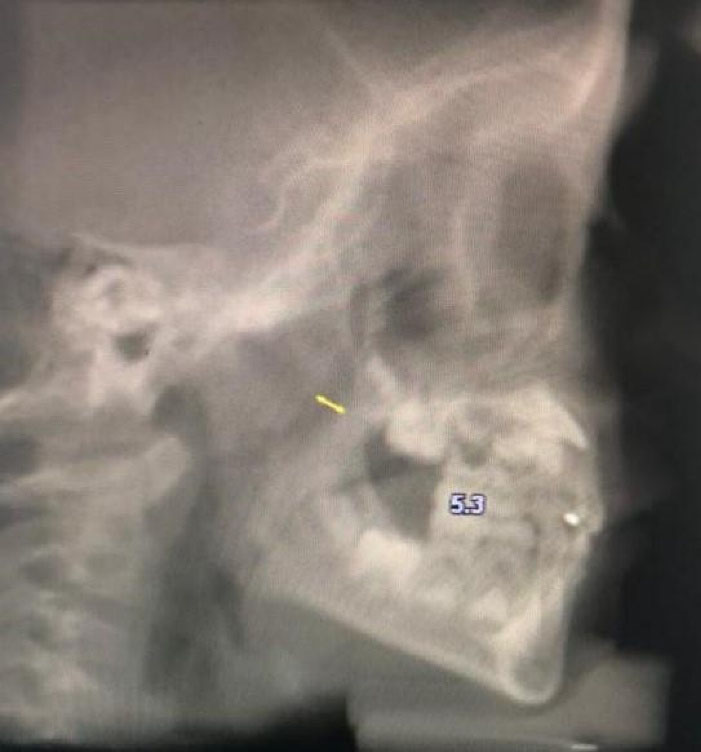

Figure 4.

Measurement of PNS-AD1 distance.

| PNS-AD1 | Shortest distance between PNS and Adenoid tissue |

| PNS-AD2 | Distance between PNS and adenoid tissue on the line perpendicular to BaS from PNS |